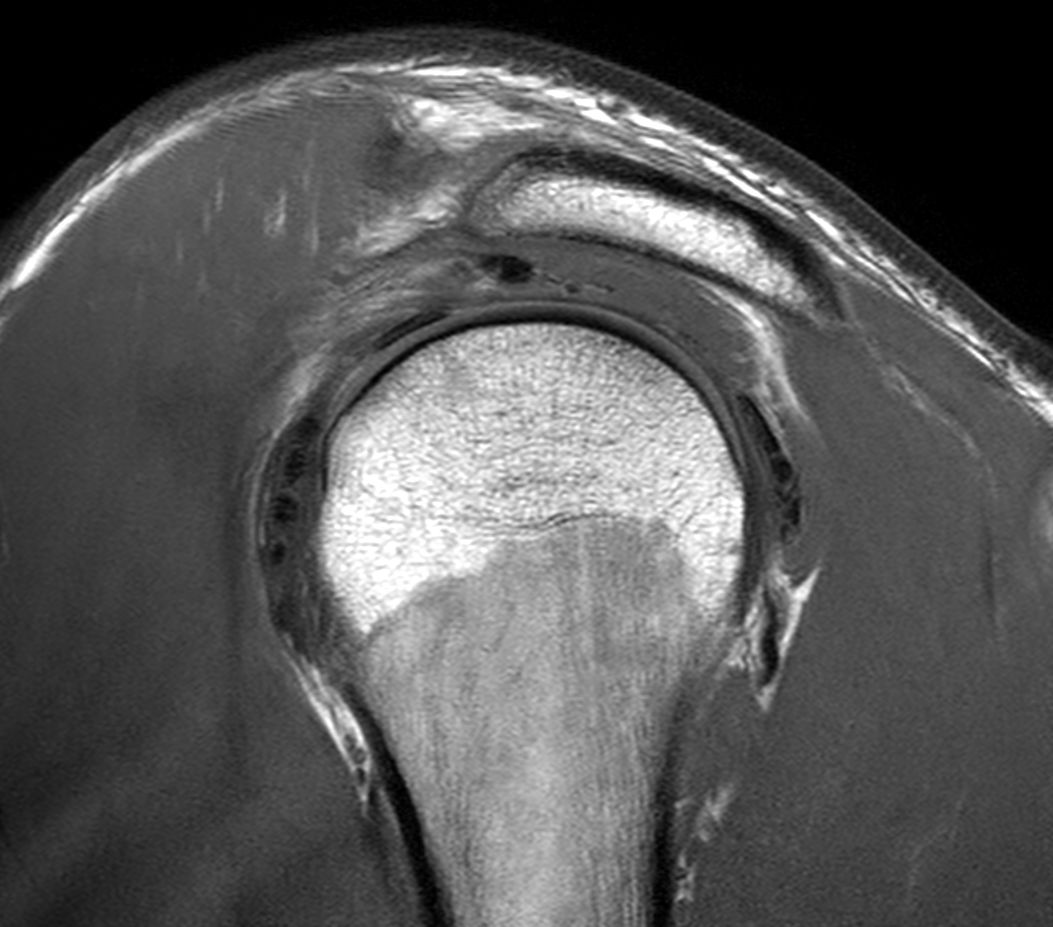

Sagittal T1w TSE